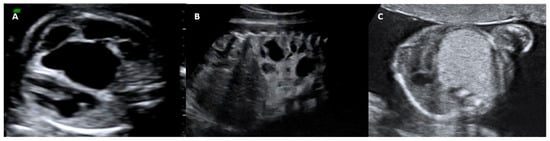

In 2002, it was hypothesized that the volume of the lesion could predict whether hydrops would occur, and the CCAM volume ratio (CVR) was developed, which is calculated by measuring the three dimensions of the lung lesion using the formula for the volume of a prolate ellipse (length × width × height × 0.52) and dividing by the fetal head circumference [8]. A CVR > 1.6 is considered predictive of the risk of hydrops and neonatal complications, while a CVR < 0.9 indicates a favorable prognosis [5]. Recently, some authors have recommended the initiation of therapy in fetuses with CCAM with a CVR > 1.4, because in some cases, lesions with a CVR of 1.4 will increase to 1.6 in approximately 7 to 14 days [9] (Figure 4).

Figure 4. Two-dimensional ultrasonography. (A) Axial plane at the level of the four-chambers and sagittal thoraco-abdominal views; CCAM volume ratio (CVR) = (length × width × height × 0.52). (B) Transventricular plane; head circumference (B). Source: the authors.